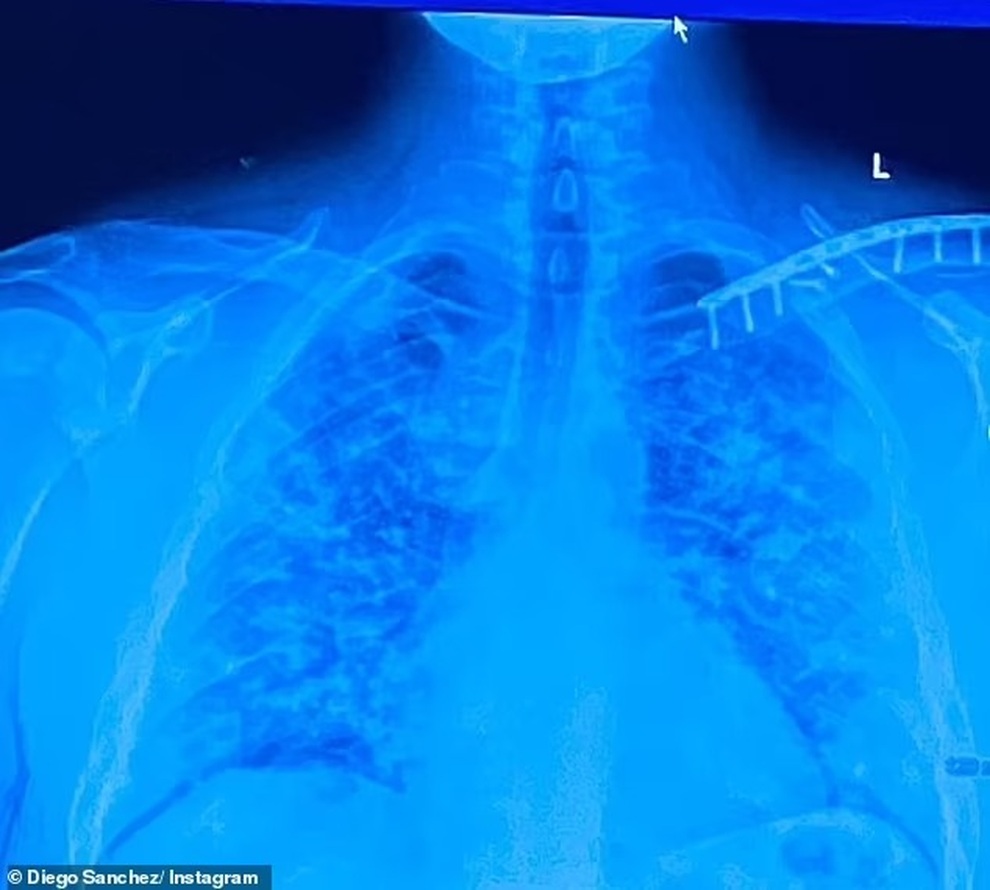

Hình ảnh chụp X-quang phổi của Sanchez cho thấy mức tàn phá của Covid-19.

"Covid không phải là trò đùa cho tất cả những ai xem thường nó", Sanchez chia sẻ thêm bức ảnh phổi anh bị tàn phá do Covid-19. Anh bày tỏ cảm giác hối hận khi mình không tiêm phòng vắc xin Covid-19 như khuyến cáo của các nhà chức trách.